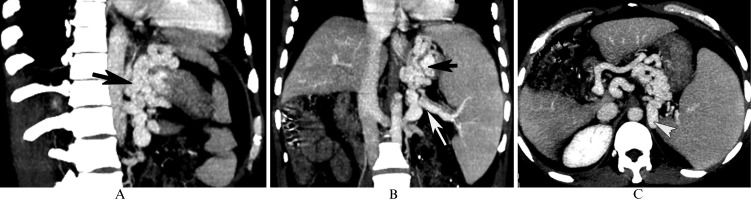

In a 48-year-old male with gastric fundic varices secondary to posthepatitic cirrhosis, the computed tomography multiplanar reformation reconstruction images show gastric fundic varices (A and B, black arrow) originating from the splenic vein (B, white arrow), which are associated with nephrogastric shunts (C, white arrowhead).